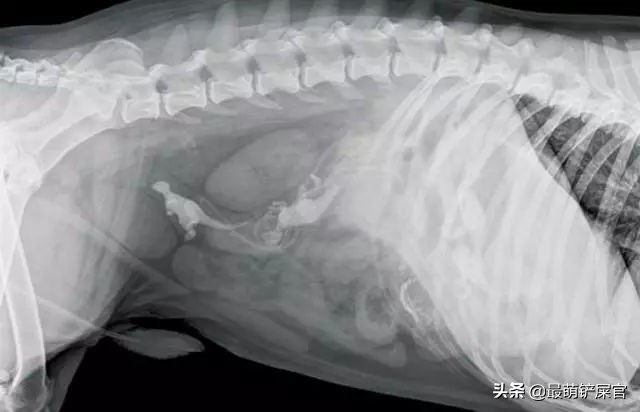

这只哈士奇吞下了一根缝衣针,大概是拆完家想剔剔牙,不过下场就是......做了个大手术,被强制住院,看你还敢不敢乱拆家!